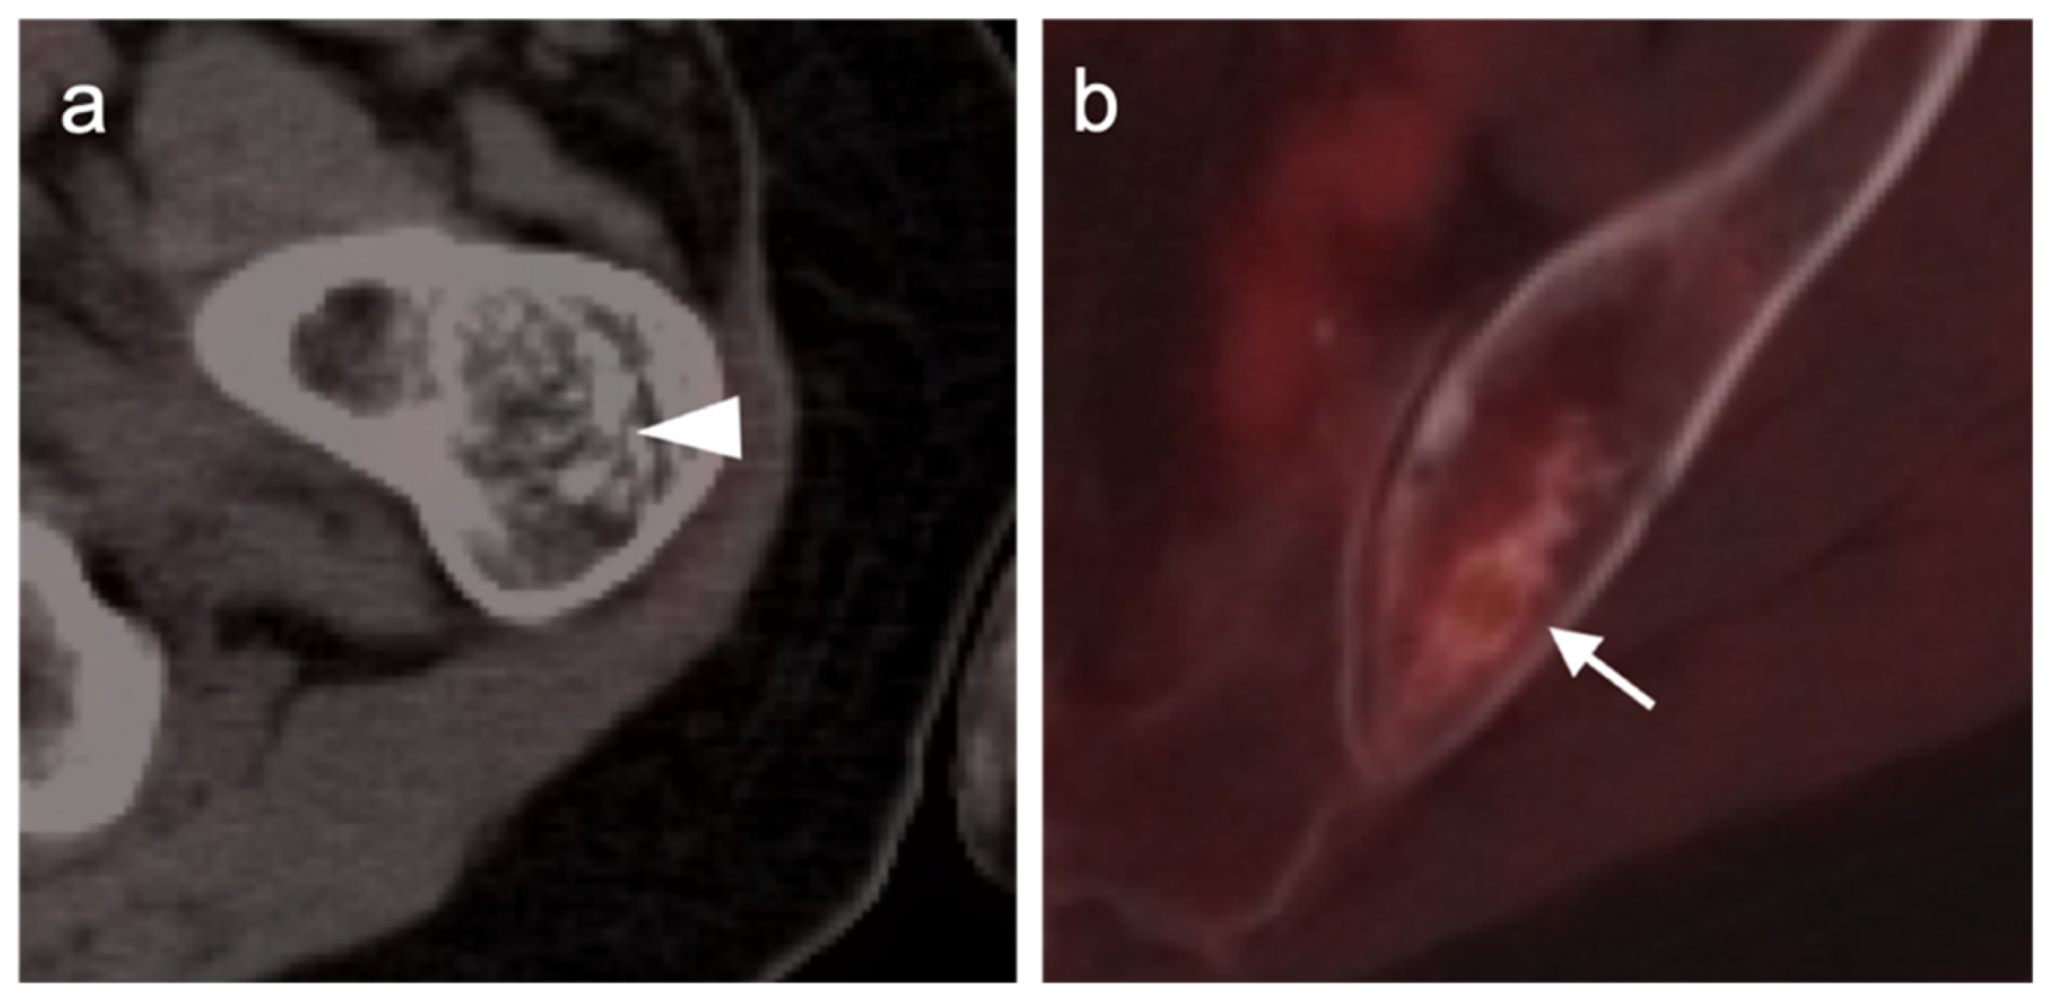

3.2. Bone Sarcomas

3.2.1. Chondrosarcoma

3.2.2. Osteosarcoma

3.2.3. Ewing Sarcoma